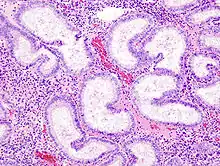

L'endomètre consiste en une couche simple d'épithélium cylindrique sur un tissu conjonctif, ce dernier étant aussi appelé stroma dans la littérature scientifique. L'épaisseur de ce tissu conjonctif évolue en fonction des niveaux d'hormones. A l'intérieur de l'utérus, des glandes cylindriques simples vont de la surface de l'endomètre jusqu'à la base du tissu conjonctif, qui acheminent aussi un apport sanguin depuis les artères spiralées utérines. Chez une personne avec un utérus et en âge de procréer, deux couches d'endomètre peuvent être distinguées. Ces deux couches sont présentes uniquement à l'intérieur de l'utérus, et non à l'intérieur des tubes utérins (anciennement appelés trompes de Fallope)[4],[5].

- La couche fonctionnelle est adjacente à la cavité utérine. Cette couche se développe à partir de cellules souches[1] à la fin des menstruations, dans la première partie du cycle menstruel. La prolifération des cellules d'endomètre, qui donne son épaississement, est provoquée par de l'œstrogène produit par les ovaires : il s'agit de la phase folliculaire du cycle menstruel. Ensuite, lors de la phase lutéale, des modifications à cette couche seront induites par du progestérone provenant du corps jaune (corpus luteum). L'endomètre est alors un environnement optimal pour l'implantation et la croissance d'un embryon. Sans embryon, cette couche se désintègre pour être évacuée lors des menstruations.

- La couche basale, sous la couche fonctionnelle et adjacente au myomètre, n'est jamais évacuée. Les cellules souches qui s'y trouvent, développent la couche fonctionnelle qui la couvre.